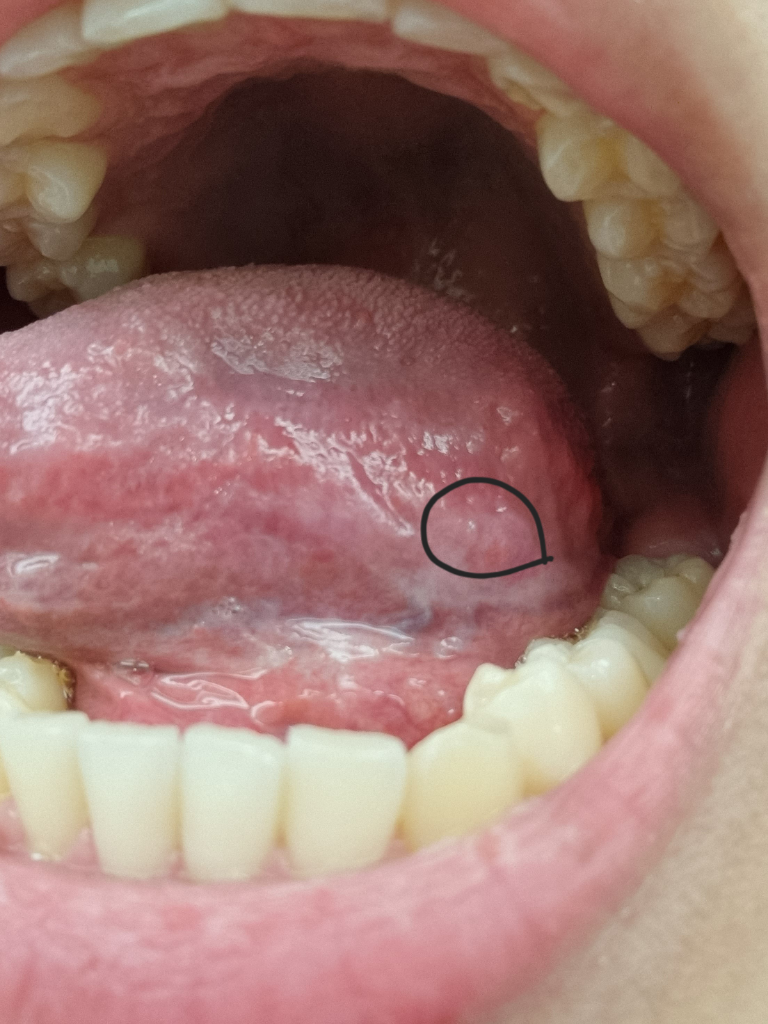

안녕하세요. 안상우 치과의사입니다.

혀 아래면에는 정맥이 지나가는 부위등이 튀어 나올수 있습니다.

병적인 증상은 아니기 때문에 너무 걱정을 하지 않으셔도 될것으로 생각되지만 해당부위에 불편감이 있다면 치과에서 진료를 받아 보는것이 좋습니다.